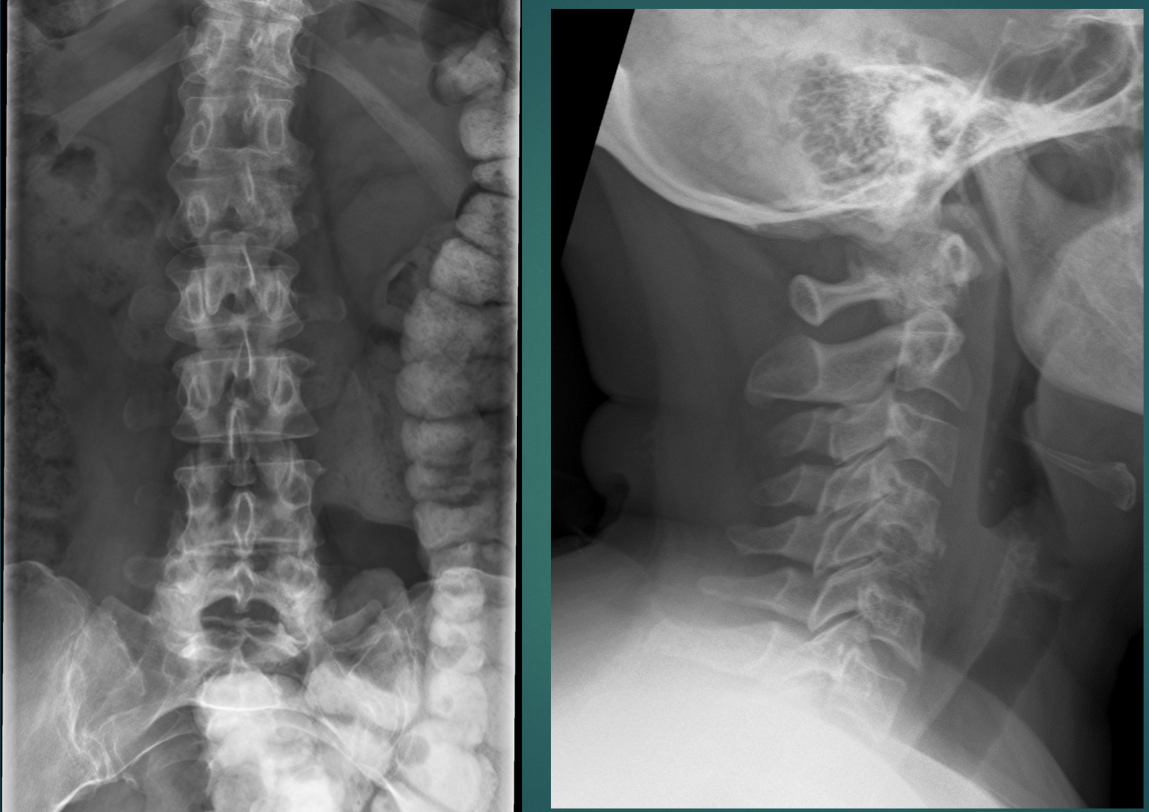

32 YO M. Several months of back pain.

• Endplate destruction

• Loss of disc height /space

• Acute kyphosis at the 2 segments (might look like retrolisthesis)

Think: infectious discitis